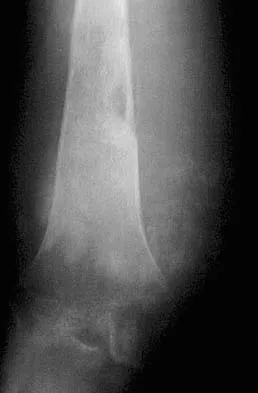

Figures 32a and 32b show the AP and lateral radiographs of an 11-year-old boy who has a severe limp, a fever, and swelling and tenderness of the thigh. Aspiration of the bone reveals purulent material. The patient has most likely been symptomatic for

Explanation

In patients with an osteomyelitic infection, radiographic findings at 1 to 5 days usually show soft-tissue swelling only. Seven to 14 days after symptoms begin, radiographs will most likely show the classic signs of acute osteomyelitis. Reactive bone formation would be expected by 6 months. Kasser JR (ed): Orthopaedic Knowledge Update 5. Rosemont, IL, American Academy of Orthopaedic Surgeons, 1996, pp 149-161.